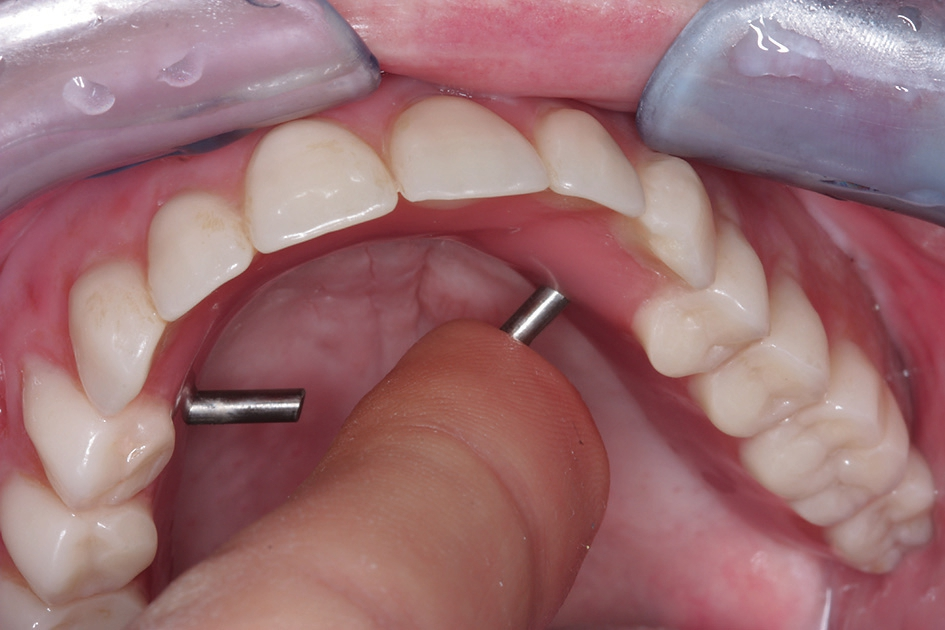

Nach vollständiger Abheilung und Anbringen der Repositions- Übertragungsaufbauten konnten die Implantate im Sinne einer Primärabformung mittels eines konfektionierten Löffels geschlossen abgeformt werden (Abb. 22). Darüber hinaus wurde eine Vorbissnahme genommen, so dass basierend auf diesen Unterlagen im Labor die Sekundärabformung als Pick-Up Abformung vorbereitet werden konnte. Hierzu erfolgte im Labor die Verbindung der Abformpfosten auf dem ersten Arbeitsmodell mit starrem Kunststoffmaterial, welcher in der Folge dann wieder getrennt wurde. Intraoral wurde dieser Trennspalt dann wieder mittels starren Kunststoffmaterials verbunden, so dass eine hohe Präzision der Abformung durch die Versteifung zwischen den Implantatpfeilern gewährleistet werden konnte (Abb. 23). Zudem erfolgte die Herstellung einer verschraubten Bissnahme, welche gerade bei grossspannigen Arbeiten ein späteres Einschleifen der Arbeit erleichtert (Abb. 24). Die Abformung wurde mit einem Polyethermaterial (Impregum, 3M ESPE, Seefeld) ausgeführt, welches sich durch eine sehr gute Formstabilität und gute Rückstellfähigkeit bei kurzer Abbindezeit auszeichnet. Im Labor wurde aus diesen Unterlagen ein Meistermodell mit Gingivamaske hergestellt und eine erste Zahnaufstellung angefertigt.

Nachdem die Passung und Ästhetik der fertigen Arbeit erneut von Behandler und Patientin überprüft worden waren, konnte die Arbeit definitiv eingesetzt werden (Abb. 26 und 27). Anschließend wurde die Patientin in den Gebrauch der Riegelvorrichtung eingewiesen sowie über die Mund- und Prothesenpflegemaßnahmen aufgeklärt (Abb. 28). Durch die Einbindung des Patienten in ein halbjährliches Recallprogramm kann in regelmäßigen Abständen der Sitz der Konstruktion und der periimplantäre Zustand überprüft werden.